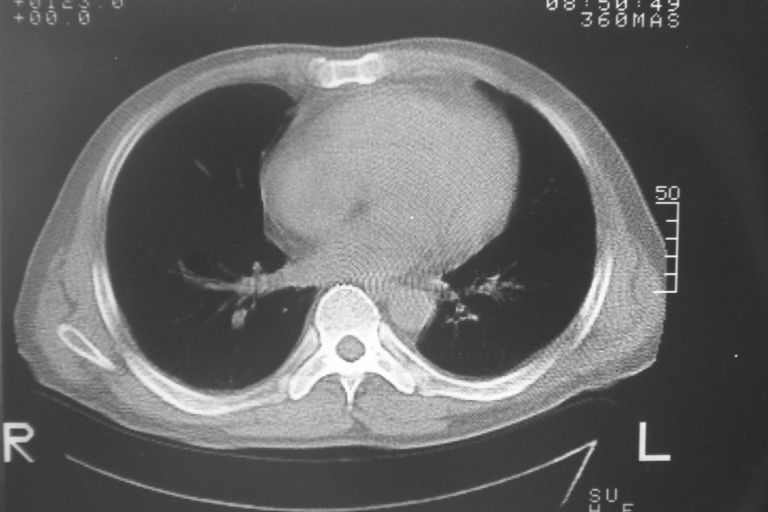

标题: CT10574:男 50岁胸部CT请会诊!

患者 男 50岁 无痛性咯血3天,无其他不适.

2心包积液

2、心包积液

2 心包积液。

2.左侧胸膜增厚.心包积液.

2心包积液,